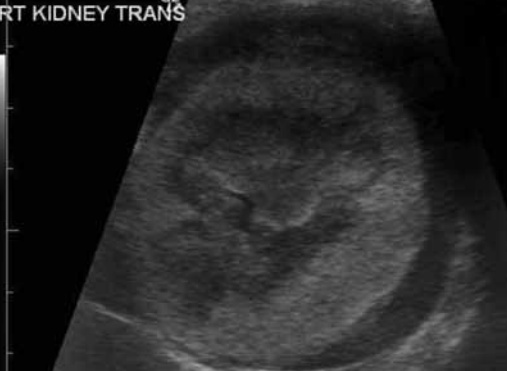

6-1. 수신증(Hydronephrosis)(그림 12)

수신증은 신우 확장 및 신배(diverticula) 확장을 의미하며, 3mm 이상 확장은 비정상으로 간주됩니다.

대부분 근위 요관의 확장(hydroureter)이 동반되며, 원인으로는 만성 감염(신우신염, 요관염), 신장 원위부 요로 폐색을 일으킬 수 있는 방광 삼각부 종양, 요관 결석, 요관 종양, 외상 또는 만성 요관염에 의한 협착, 신결석, 신우 종양 그리고 이소성 요관 등이 있습니다. 고양이에서는 요관 결석에 의한 폐색이 가장 흔한 원인으로 알려져 있습니다.

초음파 영상의 특징으로는 신장 비대, 윤곽은 대체로 매끄러우나 무에코 액체가 신우에 축적되고 원위부에 음향 증강이 있습니다. 확장 정도는 경미~중증까지 다양하며, 진행 시에는 신실질 압박이 피질을 위축시키고 신배 확장을 보입니다. 심하면 격벽성 낭성 구조를 보이며, 완전 폐색 시에는 확장된 신우 주변에 얇은 피질 띠만 남게 됩니다.